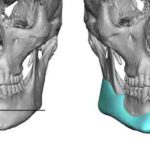

Jaw angle implants are most commonly placed through an intraoral approach without visible external scars. With bilateral posterior vestibular incisions that are up out on the cheek opposite the 2nd molar tooth, subperiosteal dissection is done to elevate the masseter muscle off of the bone. Depending upon the type of jaw angle implant being used, Read More…